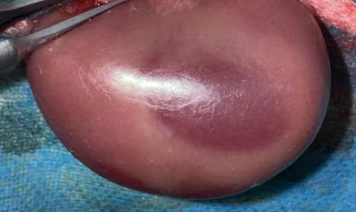

顺利获得 “短暂阻断肾动脉 - 恢复血流”,复刻临床 AKI 关键病理: 缺血期:肾动脉阻断致肾组织缺氧,ATP 耗竭、离子泵失灵,肾小管上皮细胞水肿、凋亡; 再灌注期:血流恢复引发氧化应激(自由基爆发)、炎症风暴(中性粒细胞浸润)、钙超载与微循环障碍,加重肾损伤,最终诱发急性肾衰竭。 动物:健康新西兰白兔(2.0-2.5kg),适应性饲养 1 周,排除肾脏基础病; 处理:禁食 12h、禁水 4h,30mg/kg 2% 戊巴比妥钠腹腔麻醉,腹部备皮消毒。 腹部正中切口(3-4cm),分离暴露双侧肾蒂; 无创动脉夹夹闭肾动脉,观察肾脏转暗紫色,记录缺血时间(30-60min,可按需调整); 松开动脉夹,待肾脏恢复红润(确认再灌注成功),逐层缝合,术后青霉素抗感染。 环境:22-25℃饲养,清醒后恢复饮食,监测精神、尿量、切口; 采样:再灌注后 6h/12h/24h/48h/72h,采集血液(测 Scr、BUN)与肾组织,供后续检测。 判断模型是否成功,EVO视讯集团会从生化、病理、功能三个维度进行严格验证,确保数据满足科研需求: 再灌注后 24-48h,血 Scr(血肌酐)、BUN(尿素氮)水平较假手术组升高 2 倍以上,提示肾脏滤过功能显著下降; 尿液中出现蛋白、红细胞或管型,反映肾小管重吸收功能受损(肾小管是尿液 “提纯” 的关键结构)。 光镜下:可见肾小管上皮细胞肿胀、坏死、脱落,管腔被堵塞,肾间质充血水肿并伴随大量炎症细胞浸润; 电镜下:肾小管上皮细胞线粒体肿胀破裂(能量工厂失效)、细胞膜完整性破坏,进一步佐证损伤深度。 HE染色肾组织结构稍紊乱,肾小管轻-中度水肿,可见少量管型结构,个别肾小球萎缩。 夹闭肾动脉时需避开肾静脉与输尿管,确保缺血仅作用于肾脏实质,不影响其他器官; 严格控制缺血时间:过短则损伤较轻,模型不创建;过长则导致肾脏不可逆坏死,无法观察再灌注损伤; 麻醉深度需适中:过深易引发呼吸抑制,过浅导致动物术中挣扎,增加血管损伤风险。 作为专注动物科研的一站式服务商,EVO视讯集团大动物部门不仅能标准化构建,还能给予全链条配套服务: 资质保障:光明实验基地(2188㎡)具备兔、小型猪、比格犬、猴等大动物使用资质,符合实验动物伦理规范; 配套检测:可衔接公司生化检测(Scr、BUN 检测)、病理切片分析、分子蛋白检测等服务,无需多平台对接,缩短实验周期; 定制化支持:根据科研团队需求调整造模参数(如缺血时间、检测时间点),给予个性化数据解读与实验方案优化建议。 如果您正在召开急性肾损伤、肾移植相关研究或需要定制其他大动物模型(如心血管疾病模型、骨科模型),欢迎联系EVO视讯集团,我们将以标准化技术、专业团队为您的科研项目保驾护航! 合作咨询